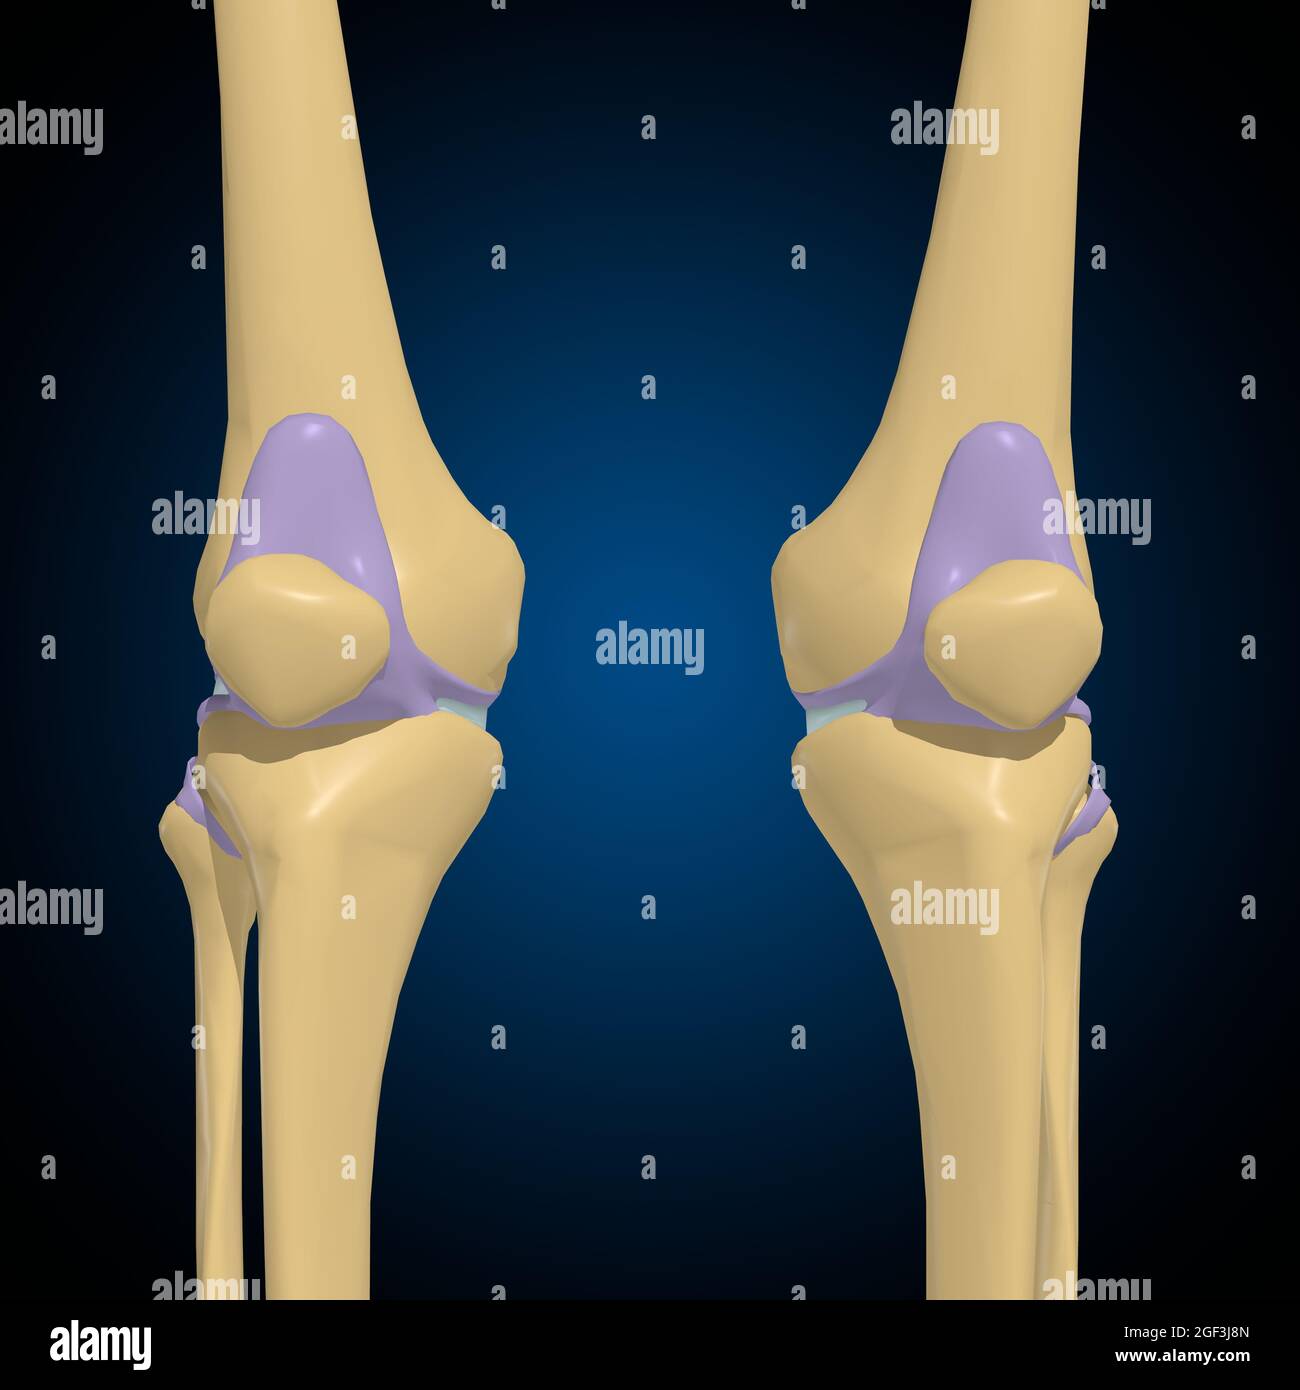

Articular capsule Anatomy For Medical Concept 3D Illustration Stock Photohttps://www.alamy.com/image-license-details/?v=1https://www.alamy.com/articular-capsule-anatomy-for-medical-concept-3d-illustration-image439559253.html

Articular capsule Anatomy For Medical Concept 3D Illustration Stock Photohttps://www.alamy.com/image-license-details/?v=1https://www.alamy.com/articular-capsule-anatomy-for-medical-concept-3d-illustration-image439559253.htmlRF2GF3J8N–Articular capsule Anatomy For Medical Concept 3D Illustration